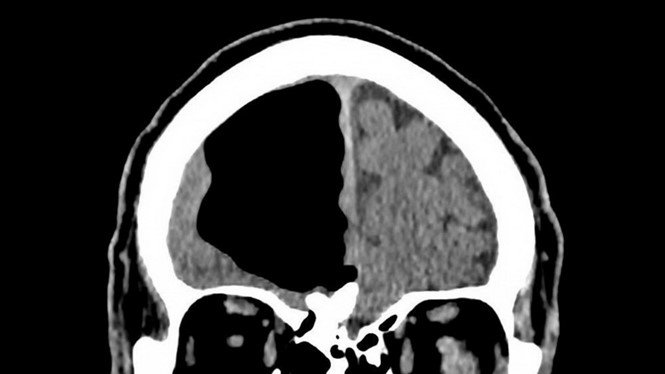

Cho tới khi ông đi chụp CT và MRI não, các bác sỹ mới phát hiện ra khoảng trống bất thường ở thùy não phải. Bác sĩ Finlay Brown thuộc khoa cấp cứu Bệnh viện Causeway và các đồng nghiệp đặt nghi vấn cho rằng cụ ông từng trải qua phẫu thuật não hoặc bị dị tật từ khi còn nhỏ, nhưng ông phủ nhận.

Khoảng trống trong thùy não phải của bệnh nhân.

Tuy nhiên, túi khí thường nhỏ và không to như lỗ hổng rộng tới 8,9 cm trong não phải của cụ ông Bắc Ireland. Kết quả chụp MRI cho thấy lỗ hổng này được hình thành từ một khối u xương lành tính.

Vị trí đặc biệt của khối u tạo thành một khoảng trống bên trong hộp sọ. Qua thời gian, những lần ho, hắt hơi của bệnh nhân sẽ đẩy một lượng khí nhỏ vào trong và ngày càng nới rộng lỗ hổng.